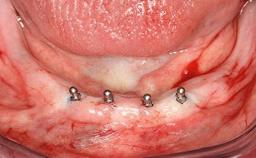

Minimally Invasive Treatment of a Patient in Her Nineties After Removing Implants Affected by Severe Peri-implantitis

A 93-year-old female patient presented in September 2010 with an enlarged swelling on the lingual side of her lower incisors. At the time, she was essentially healthy, except for reduced vision due to bilateral age-related macular degeneration. She had been a heavy smoker (about 30 cigarettes a day) for the past 20 years after becoming a widow. The patient lived at home by herself, with full-time domestic support. An extraoral examination revealed nothing adverse. Intraoral plaque control was anything but ideal, and a soft-tissue tumescence was visible around the lingual aspect of 41–42. Because the nature of the lesion was not clear, a biopsy was carried out that revealed the inflammatory nature of the lesion. The panoramic radiograph showed six irregularly distributed mandibular implants supporting a full-arch prosthesis, with various degrees of interproximal peri-implant resorption. The periapical radiograph revealed interproximal bone resorption mesially and distally to implant 41.